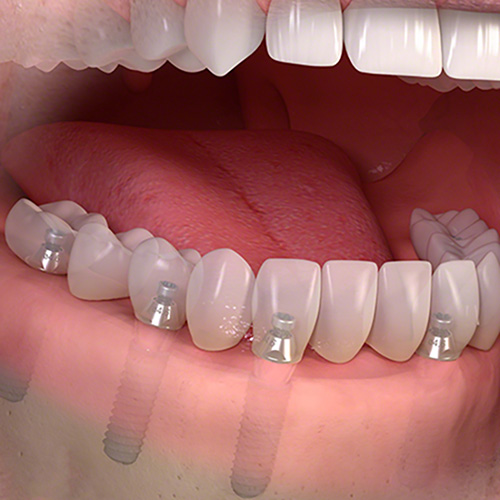

| インプラント |

![]() |

インプラントは、失った歯の部分の骨にチタン製のネジを植え込み、その上に歯の被せ物を乗せる構造をしています。

|

インプラントの一番の特徴は、入れ歯やブリッジと違い他の歯に迷惑をかけないところです。入れ歯の様に健康な歯にフックをかけたり、ブリッジの様に前後の歯を削らなくて済むので長い目で見ると一番周りの歯に優しく、長持ちすることが論文でも証明されています。 また、本来の歯の形と同じ形状大きさをしているので、異物感もなく自分の歯の様に噛むことが可能です。 |

インプラントと骨が結合するまで時間がかかるので治療期間が長くなります。 骨の中にチタン製のネジを入れるため外科処置が必要です。 |